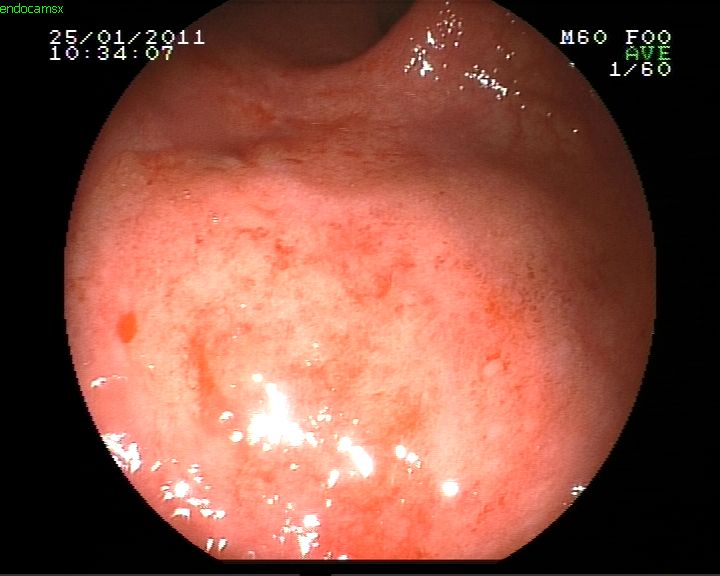

Ülseratif kolit